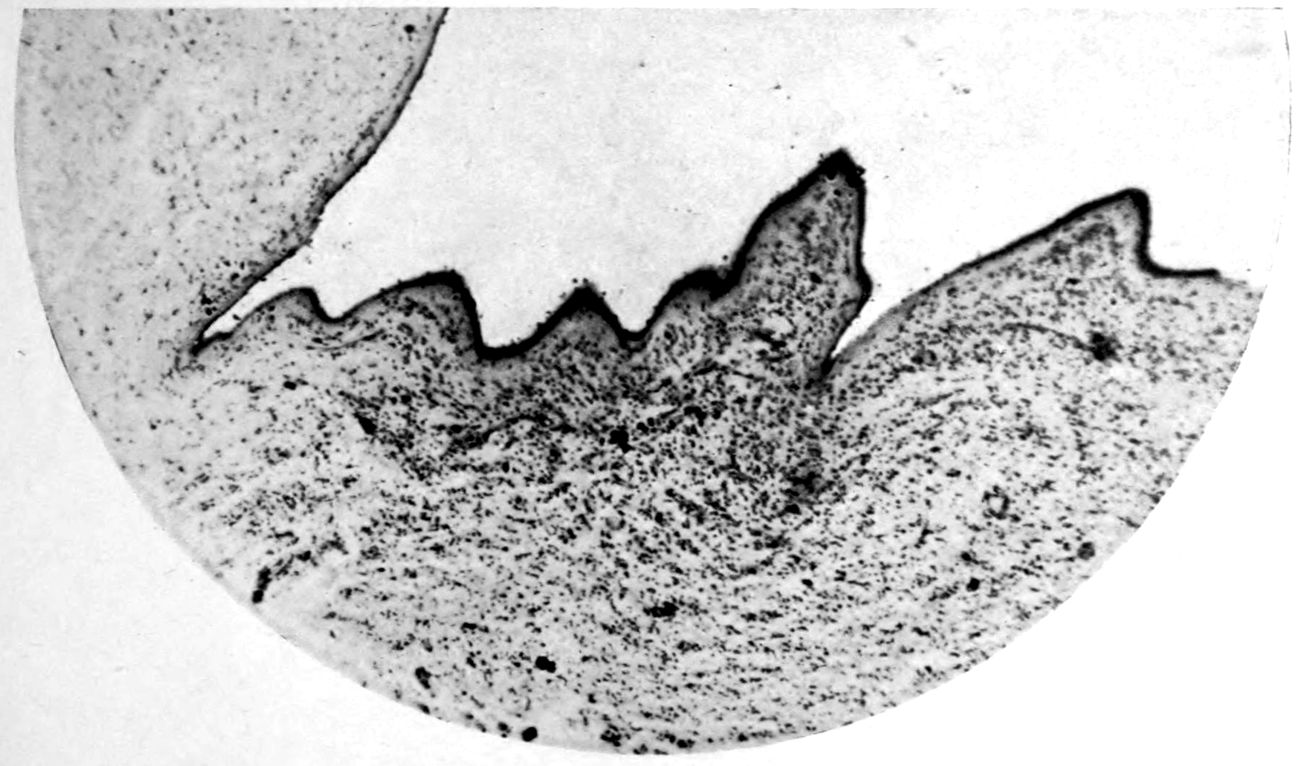

Case I. Spinal Cord (Three Levels) Showing:

A. Marginal sclerosis—effect of old meningitis now extinct.

B. Posterior column sclerosis—effect of meningitis about posterior roots also now extinct.

C. Bilateral pyramidal tract sclerosis—effect of cerebral thrombotic lesions.

Note distortion of tissues in B and C, partly artificial (tissues in places diffluent).